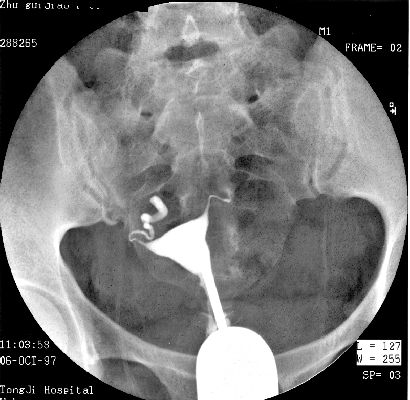

照片名称:子宫输卵管造影2

照片名称:子宫输卵管造影1

照片名称:子宫输卵管造影